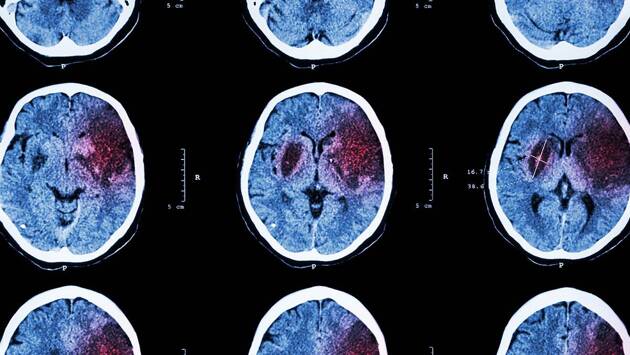

Невролог рассказал об отличиях инсульта у мужчин и женщин

Женщины и мужчины подвержены инсультам в равной степени. Об этом главный внештатный специалист невролог министерства здравоохранения РФ и Москвы, директор Института цереброваскулярной патологии и инсульта Федерального центра мозга и нейротехнологий ФМБА России Николай Шамалов сообщил на пресс-конференции на тему «Инсульт - актуальная проблема современности».

«Если говорить о том, кто более подвержен инсультам - мужчины или женщины - примерное соотношение 50 на 50 с небольшим преобладанием у женщин. Это такое заболевание, которое с равной степенью вероятности может случиться у мужчин и женщин. Другое дело, если смотреть в среднем, женщины заболевают инсультом чуть позже», - сказал Шамалов.